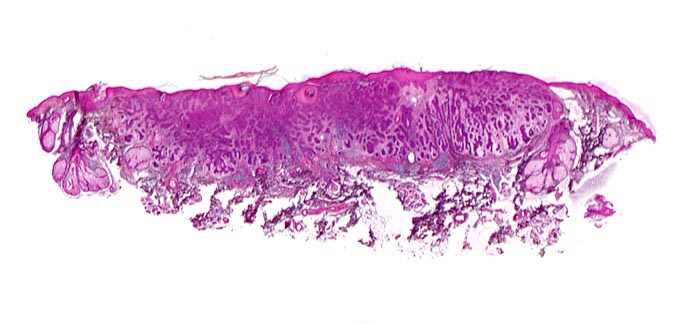

PathoPic ID 5099 - Basaliom

Basaliom

maligner Tumor

Haut, Kopf

Haut

Unmittelbar subepidermal gelegener expansiv wachsender Tumor aufgebaut aus soliden verzweigten Zellsträngen umgeben von bindegewebigem Stroma. Mehrere

Talgdrüsen am Rand des Tumors.

Derber weisser, leicht erhabener Knoten an der Nase.

Histologie

Scan